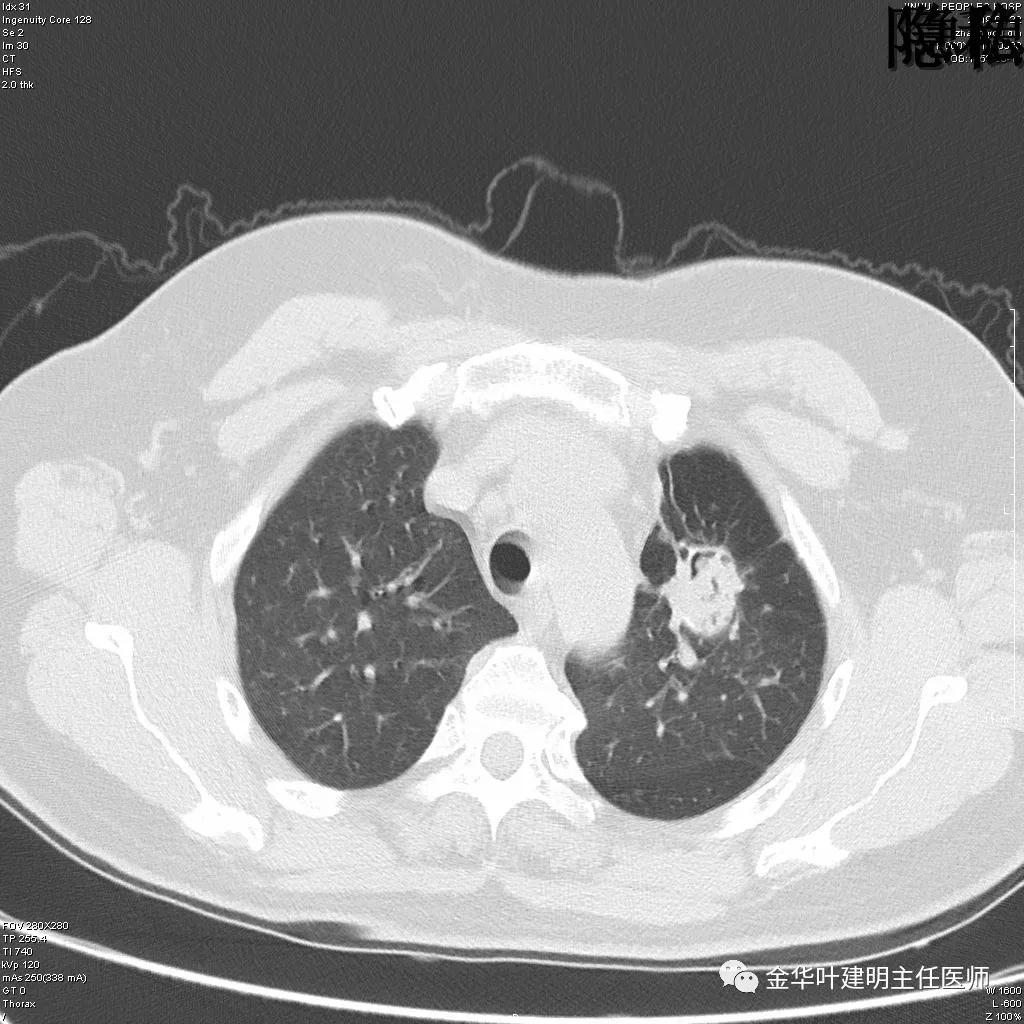

可见左肺下叶比较靠中央的部位也有一病灶,是混合磨玻璃影,偏实性,瘤肺边界清楚,是较为典型的肺癌表现。进一步的靶扫描图像如下:

靶扫描更清晰的显示细节,从影像上看,基本可以断定左下肺的是恶性肿瘤了,而且已经密度较高,长径也在3厘米以上,不能继续观察等待了!